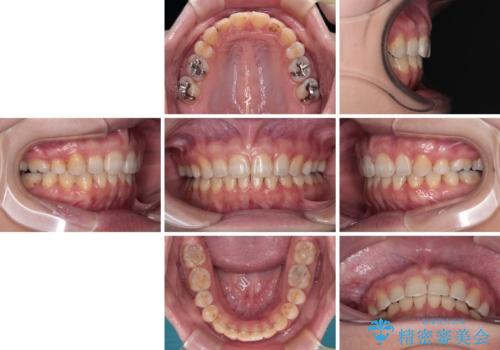

4年程度はかかるとの想定でしたが、予定通り4年ちょうどで治療を終えることができました。

上顎前歯の歯軸が大きく改善され、横顔の印象が改善されました。